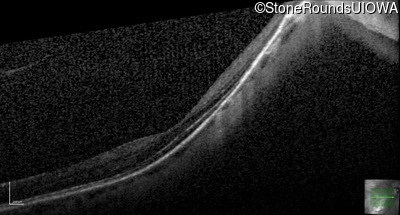

Optical Coherence Tomography - Right - 20/40 +2

Exemplar / OCT Stack

OCT Stack